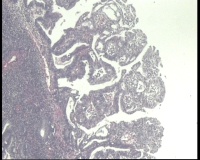

镜下见子宫内膜腺体异型增生,呈乳头状,筛网状排列,细胞核圆形,大小尚均匀,可见少量核分裂像,部分区域鳞化,间质少,部分区域无间质,间质有坏死